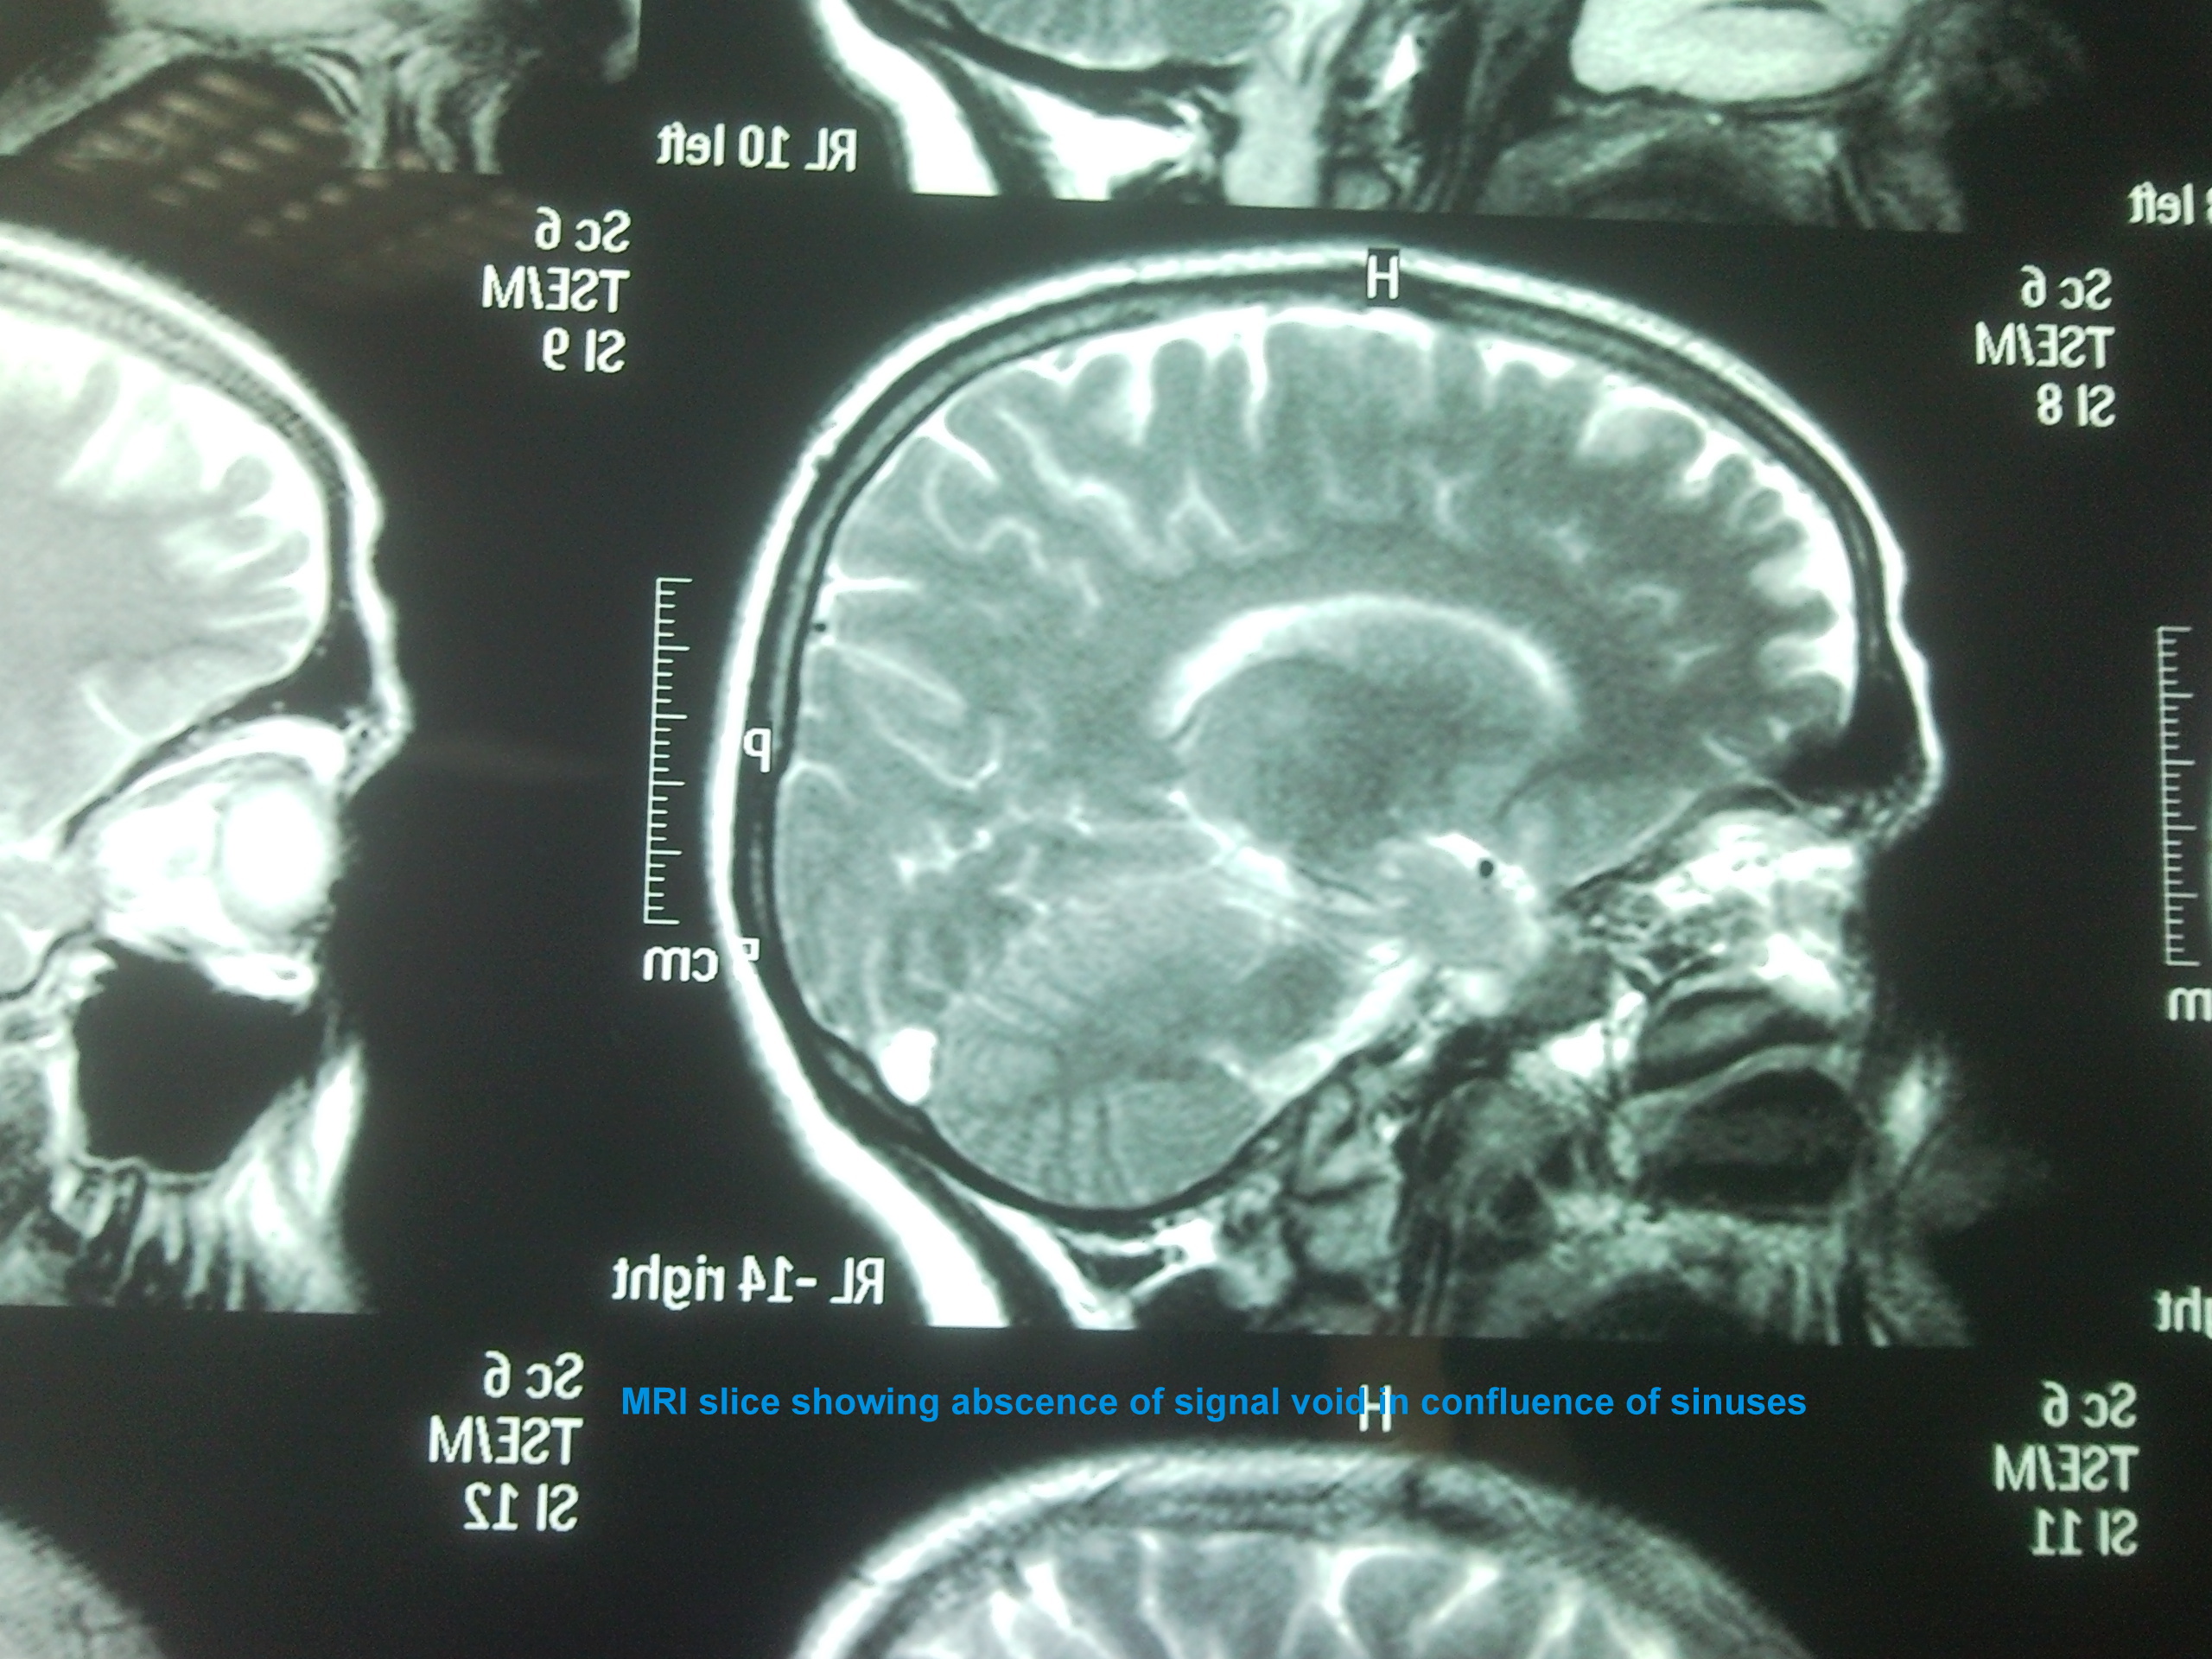

We present a case of 29 years old female patient with 20 days history of headache, projectile vomiting and low grade fever. She was referred from Swat where she was locally treated as acute pyogenic meningitis with no improvement. Patient had right 6th cranial nerve palsy and papilledema. CT brain was unremarkable and MRI brain with MR Venography showed superior sagital, confluence of sinuses and transverse sinus thrombosis.